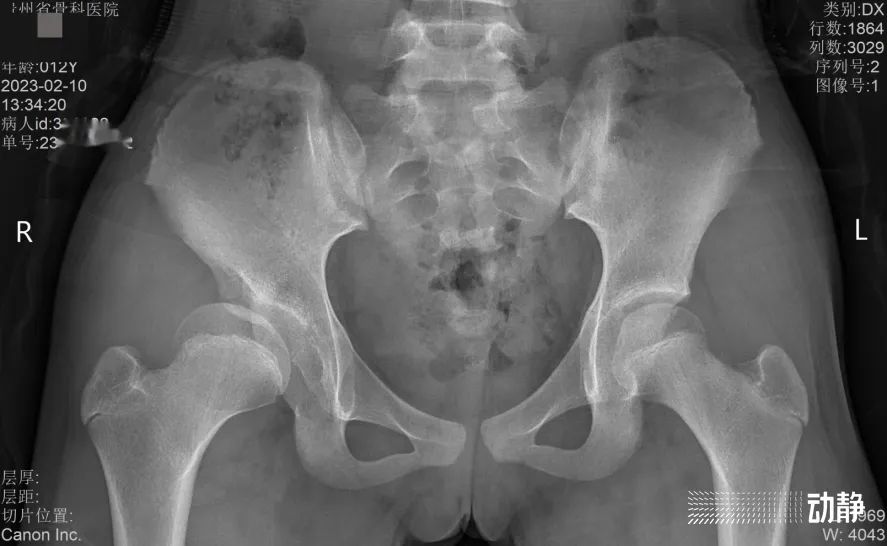

而第二例则是贵州首个采用了“积水潭入路微创三联”技术的髋关节发育不良孩子。据介绍,由于这个孩子病情发现比较晚,需要做三联截骨,把骨盆的三处都打断,是一个非常大的手术。

鲁明介绍,发育性髋关节发育不良是先天和出生后多因素共同作用的结果,发病率在千分之一,早诊断早治疗是这种病症的核心问题。